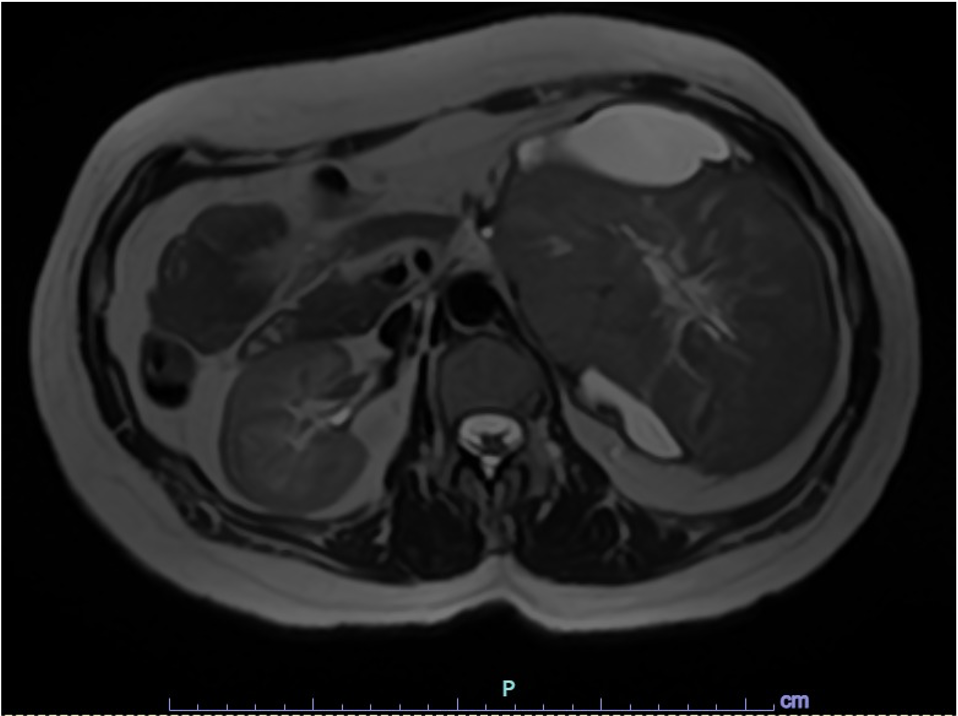

Paciente mujer de 43 años, G0-P000 con antecedentes de hipertensión arterial en tratamiento e historia familiar de cáncer (carcinoma de células de Merkel). Acude por presentar dolor punzante en flanco izquierdo de una semana de evolución. Al examen físico, se palpa masa abdominal móvil y dolorosa. La TC abdominal revela masa sólida ovoidea, de bordes definidos y aspecto encapsulado que mide 139 x 105 mm, asociada a áreas quísticas (Fig 1). Ante estos hallazgos, se realiza nefrectomía radical izquierda. Con la intención de tomar decisiones clínicas inmediatas, se realiza impronta del tumor renal en pieza operatoria observándose células tumorales poligonales con abundante citoplasma eosinofílico granular, membrana citoplasmática bien definida y bordes celulares acentuados. El resultado fue neoplasia de tipo oncocítica que favorece carcinoma cromófobo (Fig 2-5), confirmado histológicamente (Fig 6). Paciente evoluciona favorablemente.